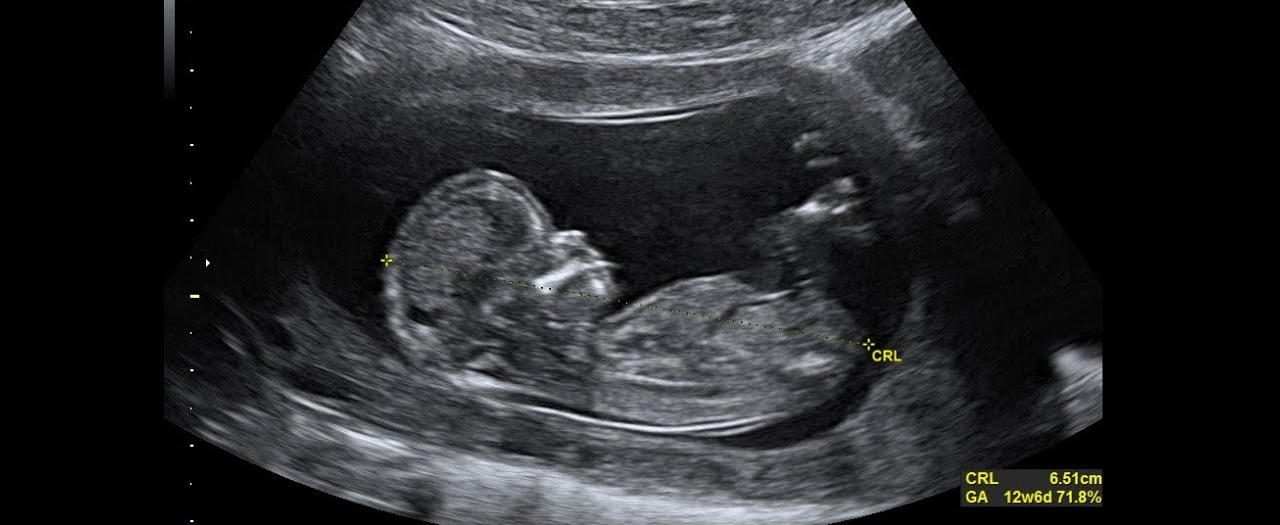

Comenzaremos con la preparación física al parto en torno a la semana 12, una vez haya pasado el primer trimestre y te hayan realizado la primera ecografía y tu médico te diga que esta todo bien. Cada mujer es diferente y también dependerá de estado de la mujer, si realizaba o no ejercicio físico antes del embarazo y su condición física.